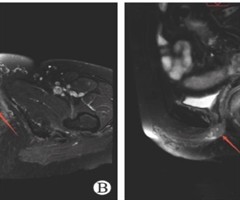

术中经食管超声发现肾癌癌栓进展而临时变更手术方案1例报告

DOI:10.3969/j.issn.1009-8291. 2025.09.016 肾癌具有向静脉系统侵袭的特性, 4%~10% 的肾癌患者合并下腔静脉癌栓, 1% 的患者合并右心房癌栓[1]。临床上常用梅奥(Mayo)分级系统根据癌栓顶端...